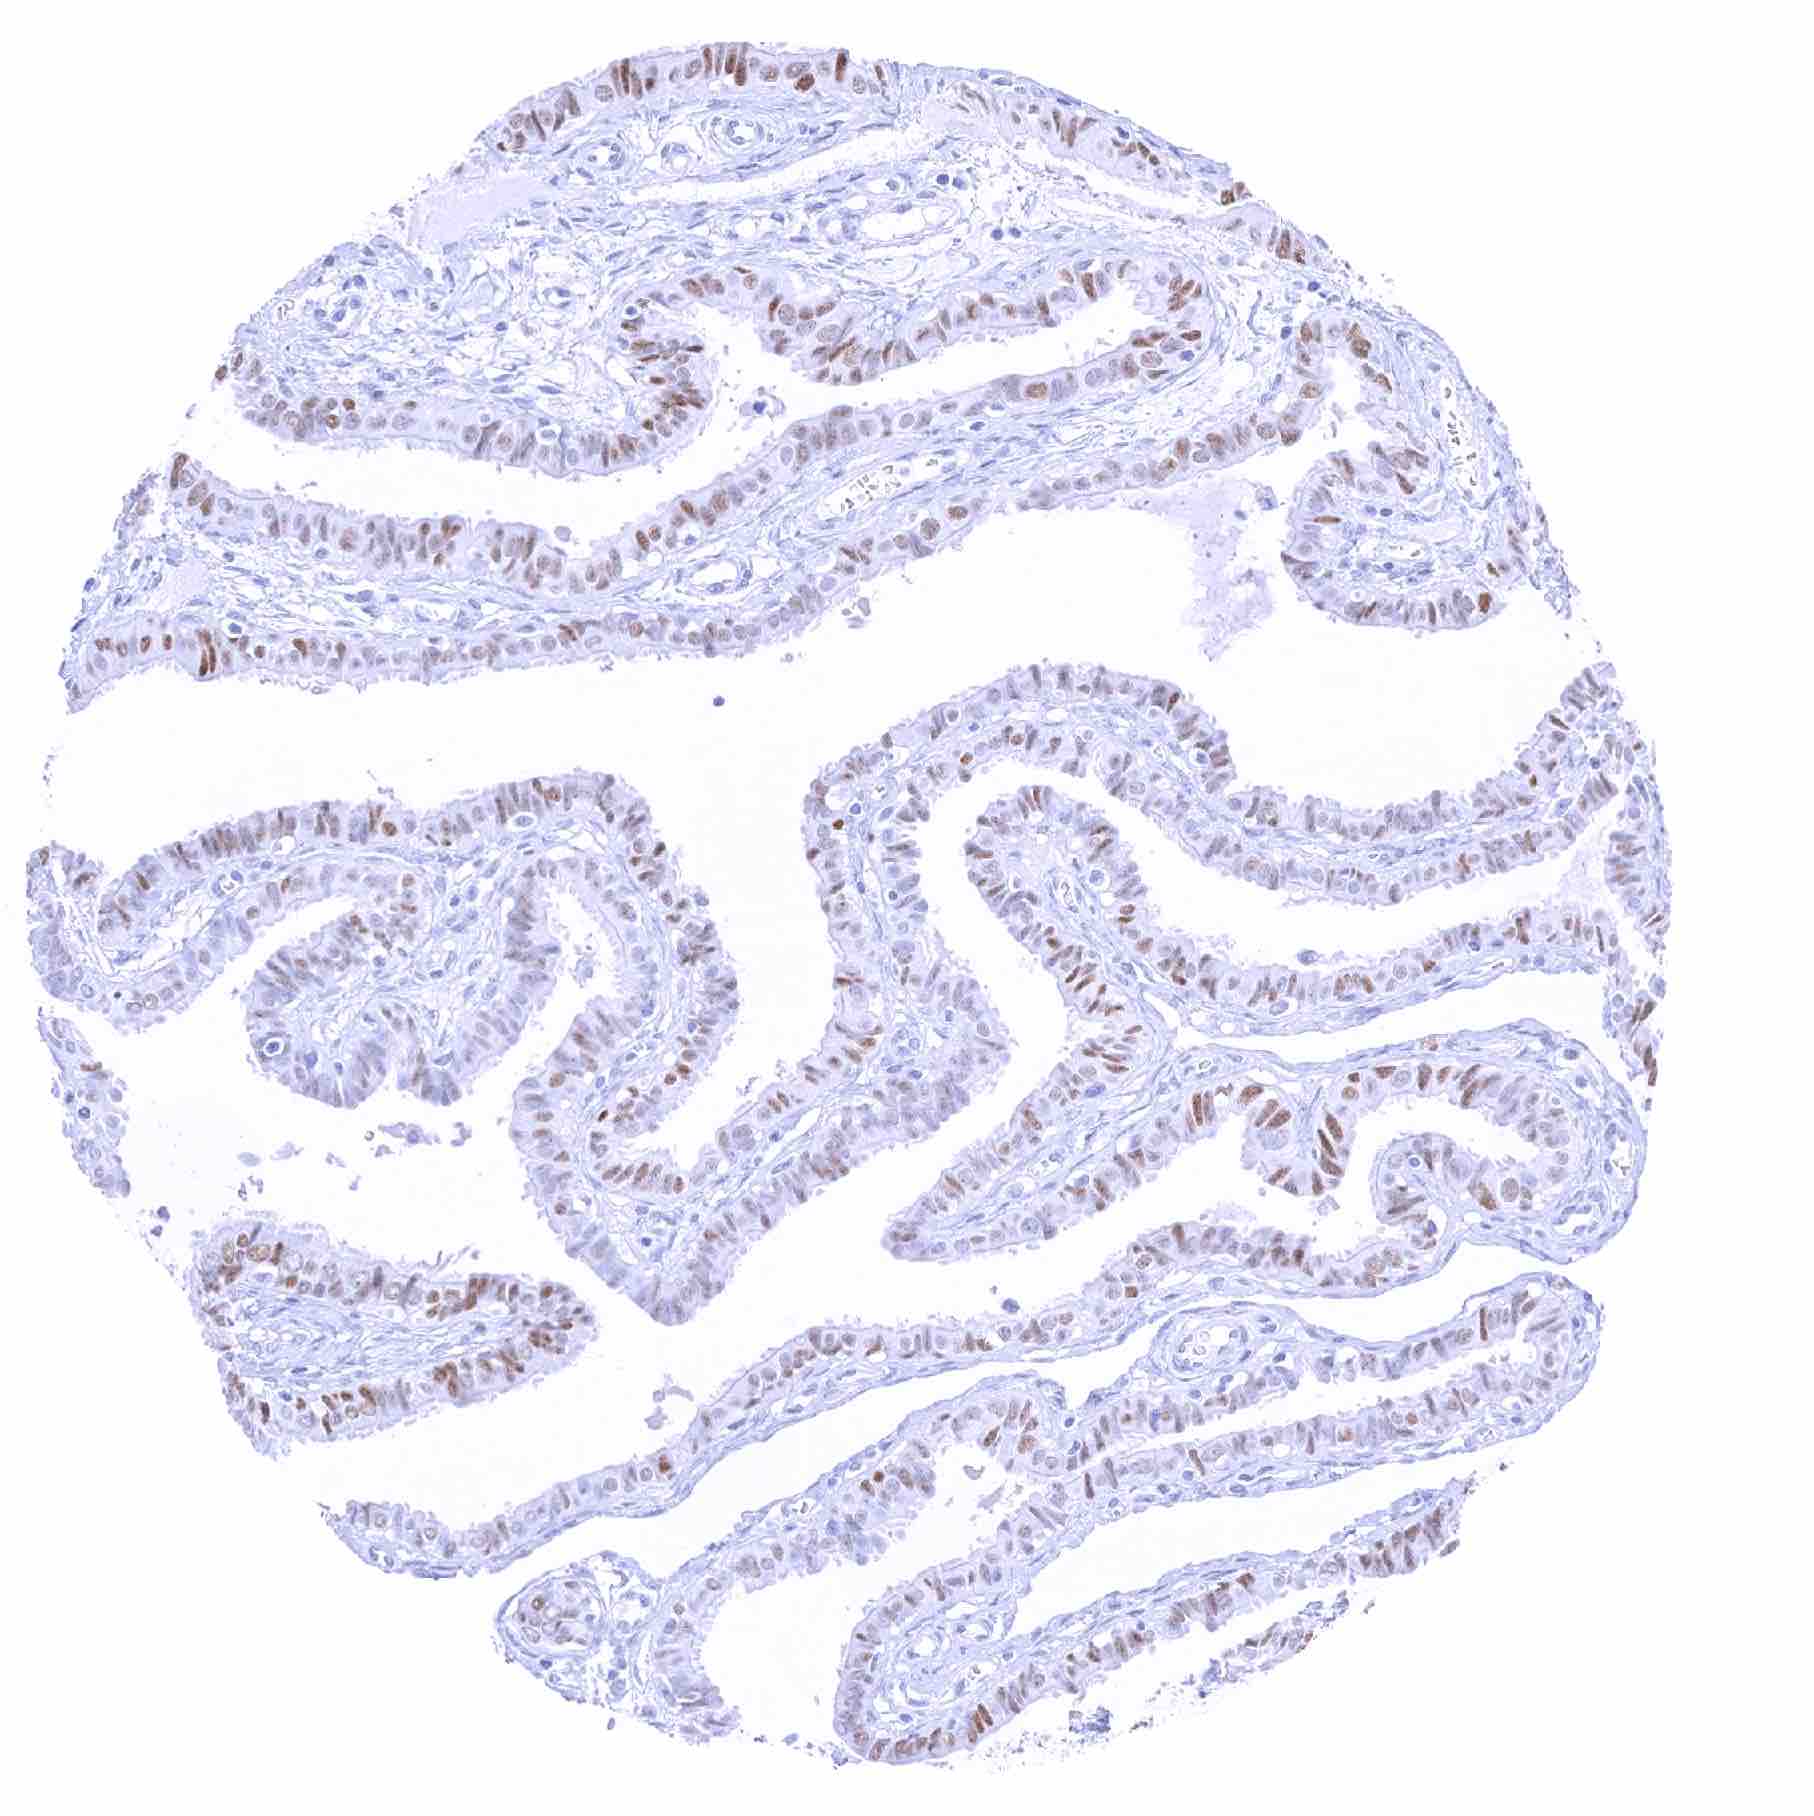

Uterus, endometrium (proliferation)